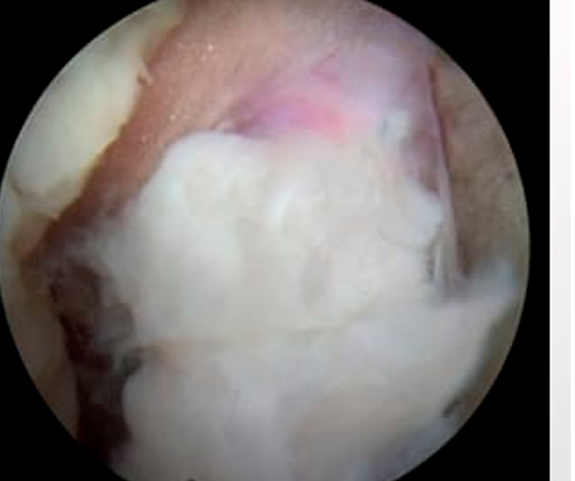

Imagem endoscópica

Antes da cirurgia: A hérnia de disco (estrutura branca) pressiona o nervo (estrutura cor de rosa ao fundo) e causa dor